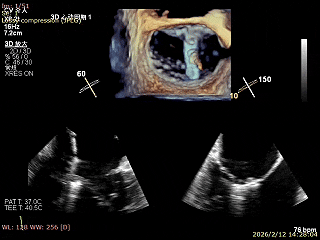

二尖瓣三维视图

2区彩色血流